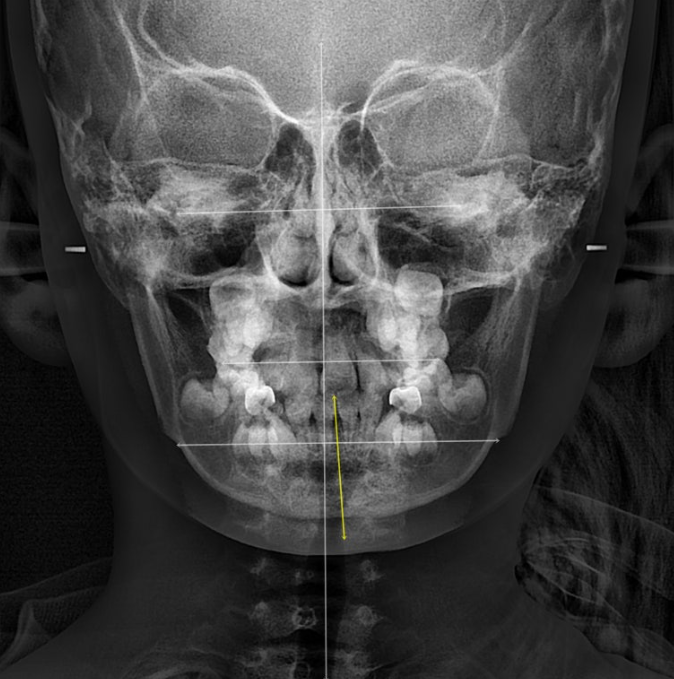

엑스레이에서 아래턱의 골격적 비대칭으로 진단이 되었습니다.

23.12